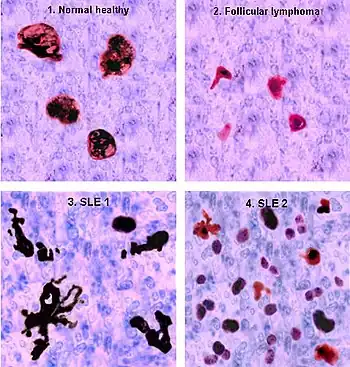

Tingible body macrophages (TBMs) – large phagocytic cells in the germinal centers of secondary lymph nodes – express CD68 protein. These cells normally engulf B cells that have undergone apoptosis after somatic hypermutation. In some people with SLE, significantly fewer TBMs can be found, and these cells rarely contain material from apoptotic B cells. Also, uningested apoptotic nuclei can be found outside of TBMs. This material may present a threat to the tolerization of B cells and T cells. Dendritic cells in the germinal center may endocytose such antigenic material and present it to T cells, activating them. Also, apoptotic chromatin and nuclei may attach to the surfaces of follicular dendritic cells and make this material available for activating other B cells that may have randomly acquired self-protein specificity through somatic hypermutation.[88] Necrosis, a pro-inflammatory form of cell death, is increased in T lymphocytes, due to mitochondrial dysfunction, oxidative stress, and depletion of ATP.[89]

Germinal centers

In healthy conditions, apoptotic lymphocytes are removed in germinal centers (GC) by specialized phagocytes, the tingible body macrophages (TBM), which is why no free apoptotic and potential autoantigenic material can be seen. In some people with SLE, a buildup of apoptotic debris can be observed in GC because of an ineffective clearance of apoptotic cells. Close to TBM, follicular dendritic cells (FDC) are localised in GC, which attach antigen material to their surface and, in contrast to bone marrow-derived DC, neither take it up nor present it via MHC molecules.[96]

Autoreactive B cells can accidentally emerge during somatic hypermutation and migrate into the germinal center light zone. Autoreactive B cells, maturated coincidentally, normally do not receive survival signals by antigen planted on follicular dendritic cells and perish by apoptosis. In the case of clearance deficiency, apoptotic nuclear debris accumulates in the light zone of GC and gets attached to FDC.[96]

This serves as a germinal centre survival signal for autoreactive B-cells. After migration into the mantle zone, autoreactive B cells require further survival signals from autoreactive helper T cells, which promote the maturation of autoantibody-producing plasma cells and B memory cells. In the presence of autoreactive T cells, a chronic autoimmune disease may be the consequence.[96][97]

Several techniques are used to detect ANAs. The most widely used is indirect immunofluorescence (IF). The pattern of fluorescence suggests the type of antibody present in the people's serum. Direct immunofluorescence can detect deposits of immunoglobulins and complement proteins in people's skin. When skin not exposed to the sun is tested, a positive direct IF (the so-called lupus band test) is evidence of systemic lupus erythematosus.[101]

The lupus erythematosus (LE) cell test was commonly used for diagnosis, but it is no longer used because the LE cells are only found in 50–75% of SLE cases and they are also found in some people with rheumatoid arthritis, scleroderma, and drug sensitivities. Because of this, the LE cell test is now performed only rarely and is mostly of historical significance.[106]